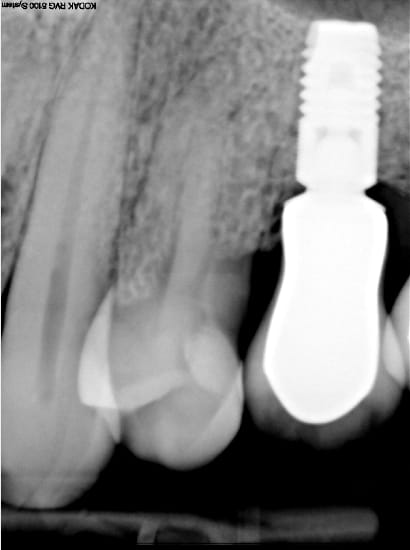

qui pose des implants baby?

De moins de 8mm et quels sont vos obserevations, taux d'échecs, en foction du rapport c/i , qualité de l'os...

merci de vos observations

je pose des astra 6 mm, pour l'instant pas de soucis, mais j'en ai pas posé énormément.

par contre des 8 mm j'en ai posé pas mal.